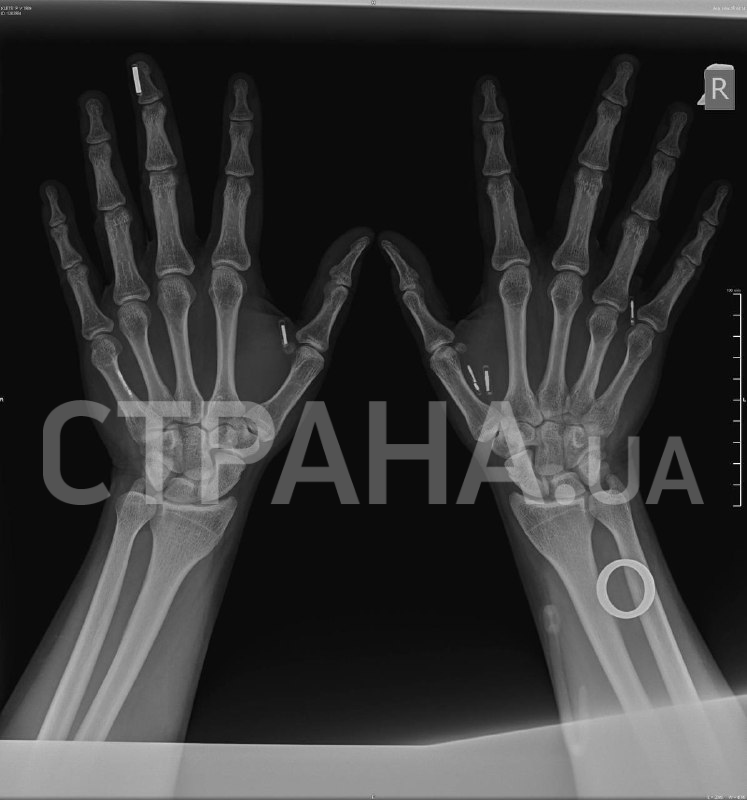

– Когда я ехал на пресс-брифинг, где мне вживили восьмой чип, очень переживал, что столкнусь со шквалом критики, что меня будут поджидать какие-то фанатики, чтобы напасть на меня или еще что-то. Но реакция была совсем иной, я, честно, даже не ожидал, что все к этому отнесутся с пониманием и интересом. Дело в том, что имплантаты, электронные или нет, давно существуют в нашей жизни: люди ставят себе зубы, ремонтируют кости. Вы же не отказываетесь от гипса, потому что он надевается на руку. Люди не отказываются от спиц в руке, хотя это то же самое, что вживить чип. Я не до конца понимаю, в чем разница между имплантируемой электроникой и любым другим имплантом, но все равно уважаю мнение этих людей, пусть оно будет.

– У меня есть чипы и магниты. С чипами вообще все просто: более десяти лет назад в передаче "Разрушители мифов", ещё тогда чипы более простой конструкции проверяли на то, влияет ли на них аппарат МРТ. Нет, он не влияет, функциональность сохраняется, человек этого даже не ощущает.